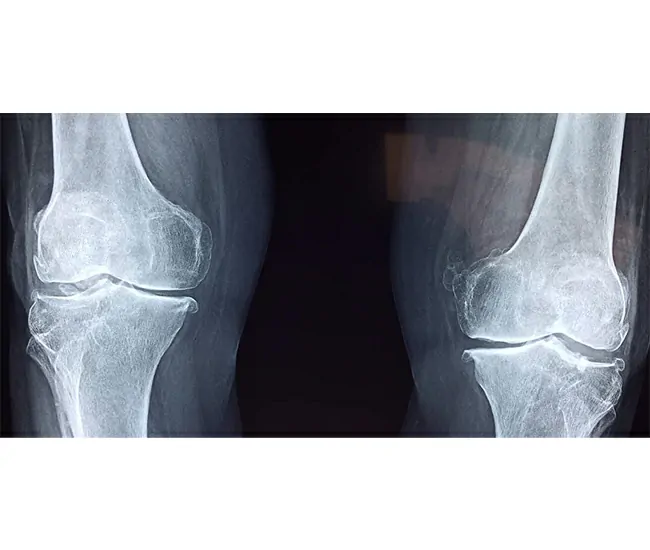

Knee osteoarthritis (OA) is a degenerative joint disease caused by the gradual breakdown of cartilage, ligaments, and bones in the knee joint. It leads to pain, stiffness, swelling, and reduced mobility.

1. Cartilage Degeneration – Loss of cushioning in the knee joint.

4. Osteophyte Formation (Bone Spurs) – Leads to stiffness & pain.

6. Deformity in Severe Cases – Bow-legged or knock-knee appearance.